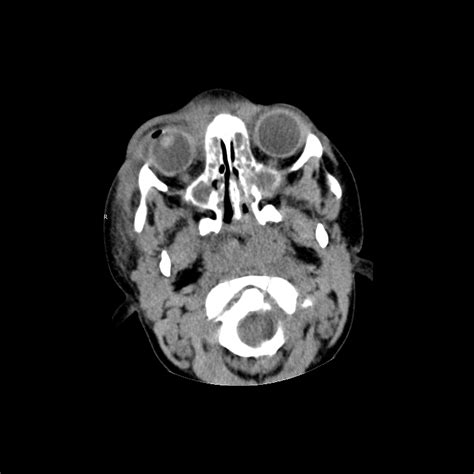

⚠️ Note: Differentiation often requires diagnostic imaging such as a CT scan or MRI. Always consult with an ophthalmologist or emergency physician to confirm the diagnosis and determine the appropriate treatment pathway.

When you arrive at the hospital displaying Orbital Cellulitis Symptoms, physicians will perform a thorough ocular exam to check for pupillary reaction and vision clarity. Imaging is the gold standard for diagnosis. A high-resolution CT scan provides the clearest picture of whether the infection has localized into an abscess, which may require surgical intervention.